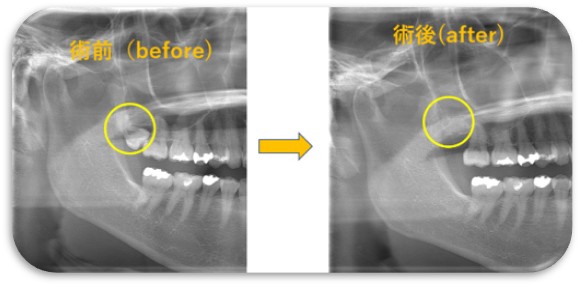

親知らず抜歯に関しては上下、骨に埋まってる難しい歯を含めて多数の症状に対応可能となっており、大和市内市外からも患者さんが来られるそうです。